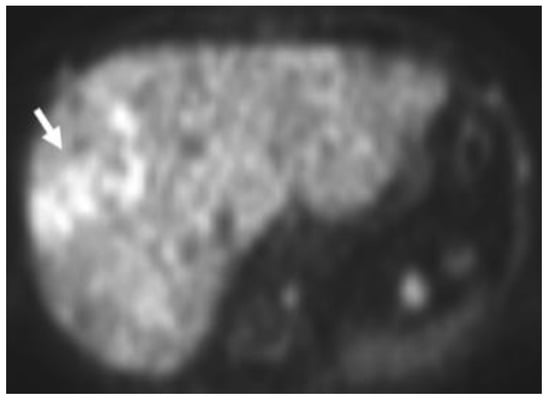

Detection of Loco-Regional Disease and Distant Metastases